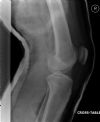

Dislocated Right Knee - Lateral view (2)